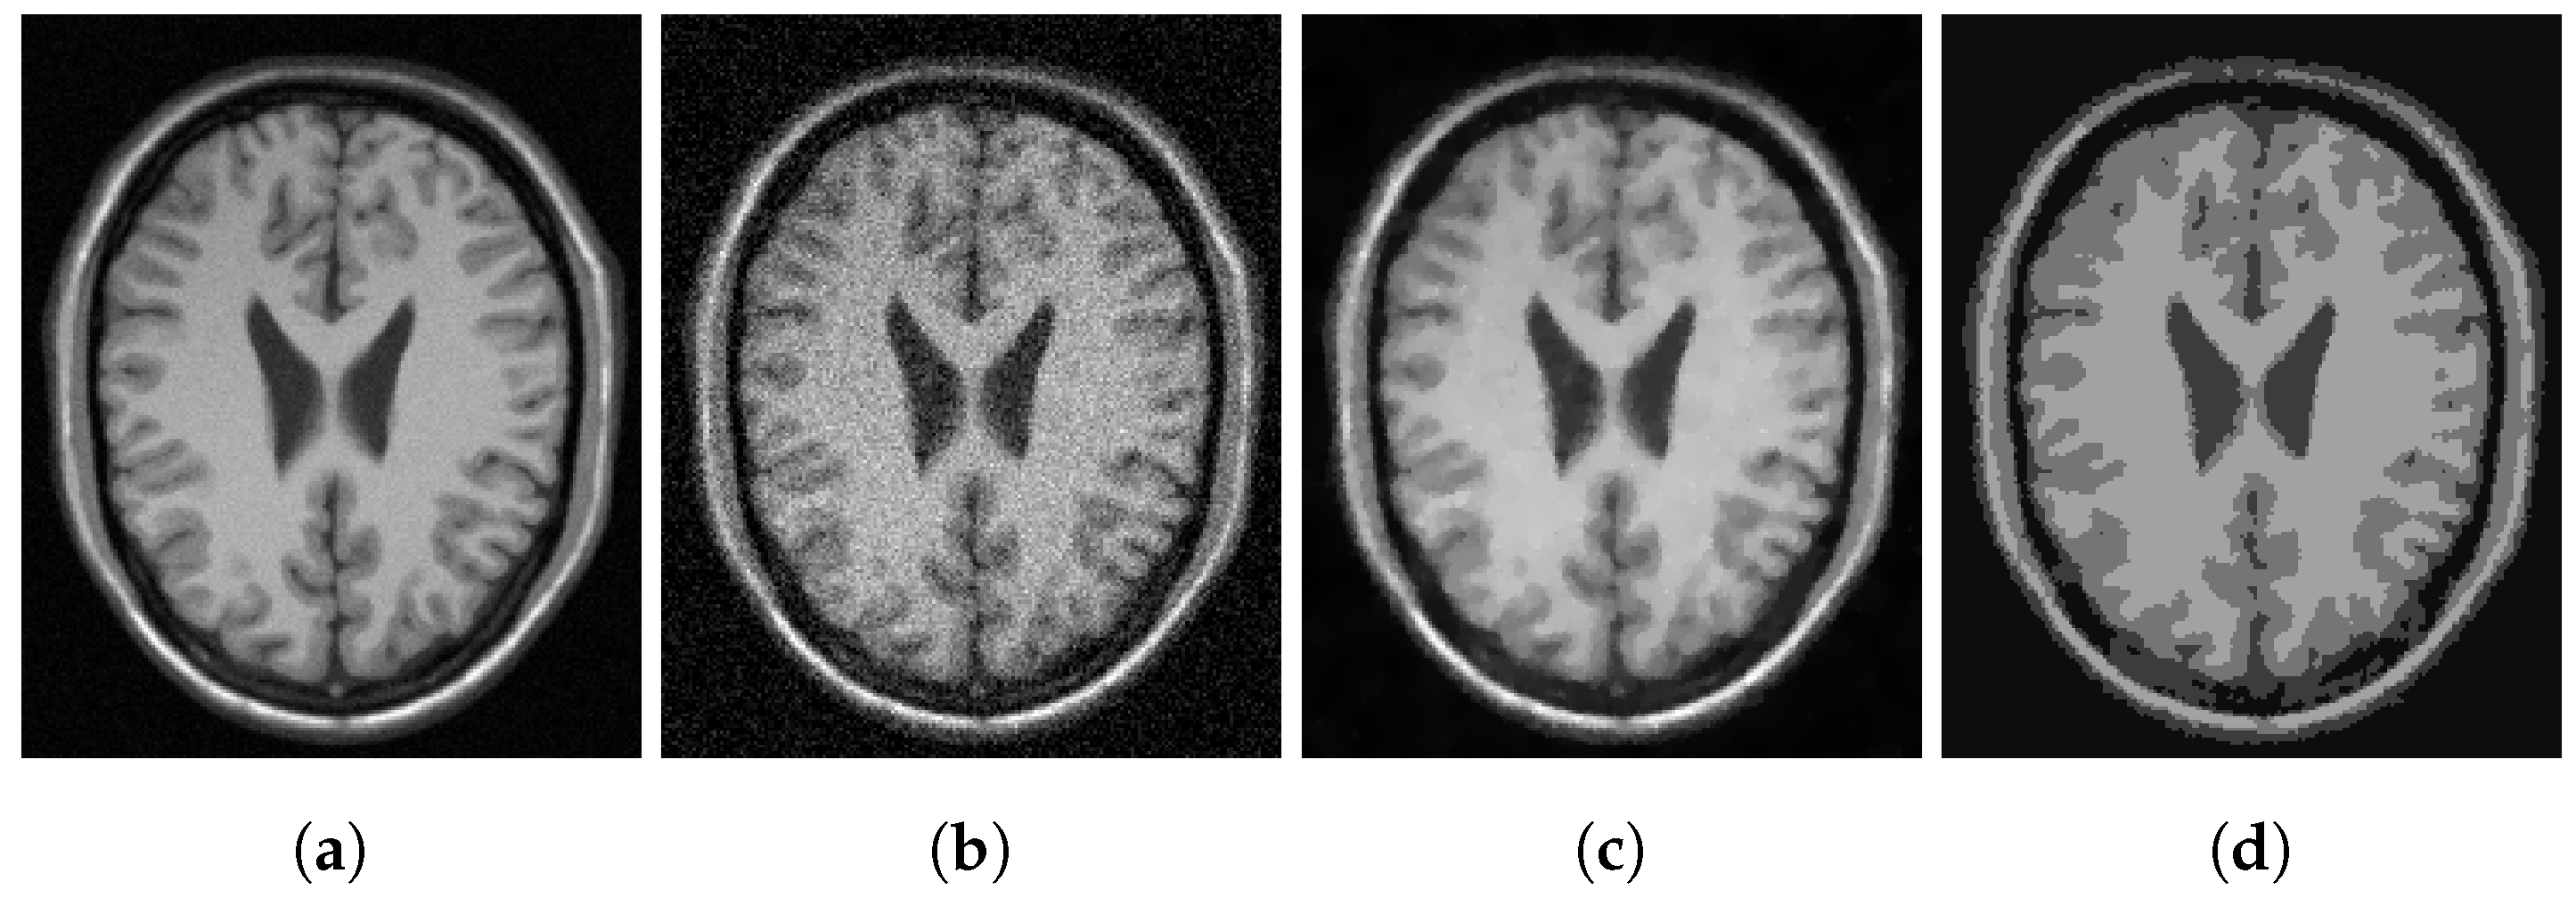

In Figure 3, Figure 4 and Figure 5, we show some examples of multiphase segmentation on MRI images of the brain. In all cases, we add Gaussian noise with mean 0 and standard deviation 17 and run the noisy image as input to both for all models but the CRCV model (as this is a two-phase model only). The output is then given as input to the k-means algorithm with . We show the clustering output in the final column of the relevant figures. We see that the segmentation result of our model is better at finding some of the finer edges; for example, the white matter segmentation from our model is in general more detailed than the segmentation from the competing ones.

Figure 4.

MRI segmentation: (a) Clean image. (b) Noisy image used as input to the models. (c) Output of CCZ. (d) CCZ after thresholding. (e) Output of CNC. (f) CNC after thresholding. (g) Output of T-ROF. (h) T-ROF after thresholding. (i) Output g of our model. (j) Output of our model. (k) Output of our model. (l) Ours after thresholding.